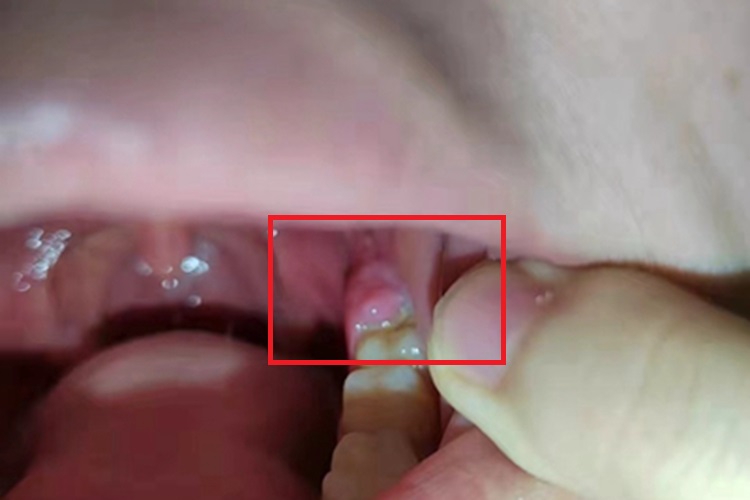

急性局限型冠周炎可使牙龈局部出现异常凸起的包块,大小不一,形状不规则,表面肿胀,多呈淡红色、粉红色。自觉有胀痛不适,进食咀嚼、吞咽、开口活动时疼痛加重。

阻生智齿及智齿在萌出过程中,牙冠可部分或全部被龈瓣覆盖,龈瓣与牙冠之间形成较深的盲袋,食物及细菌极易嵌塞于盲袋内,加上冠部牙龈常因咀嚼食物而损伤,形成溃疡。当全身抵抗力下降、局部细菌毒性增强时,可引起急性局限型冠周炎。